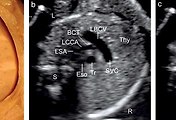

left brachiocephalic vein fetal ultrasound  (0) 2020.05.04